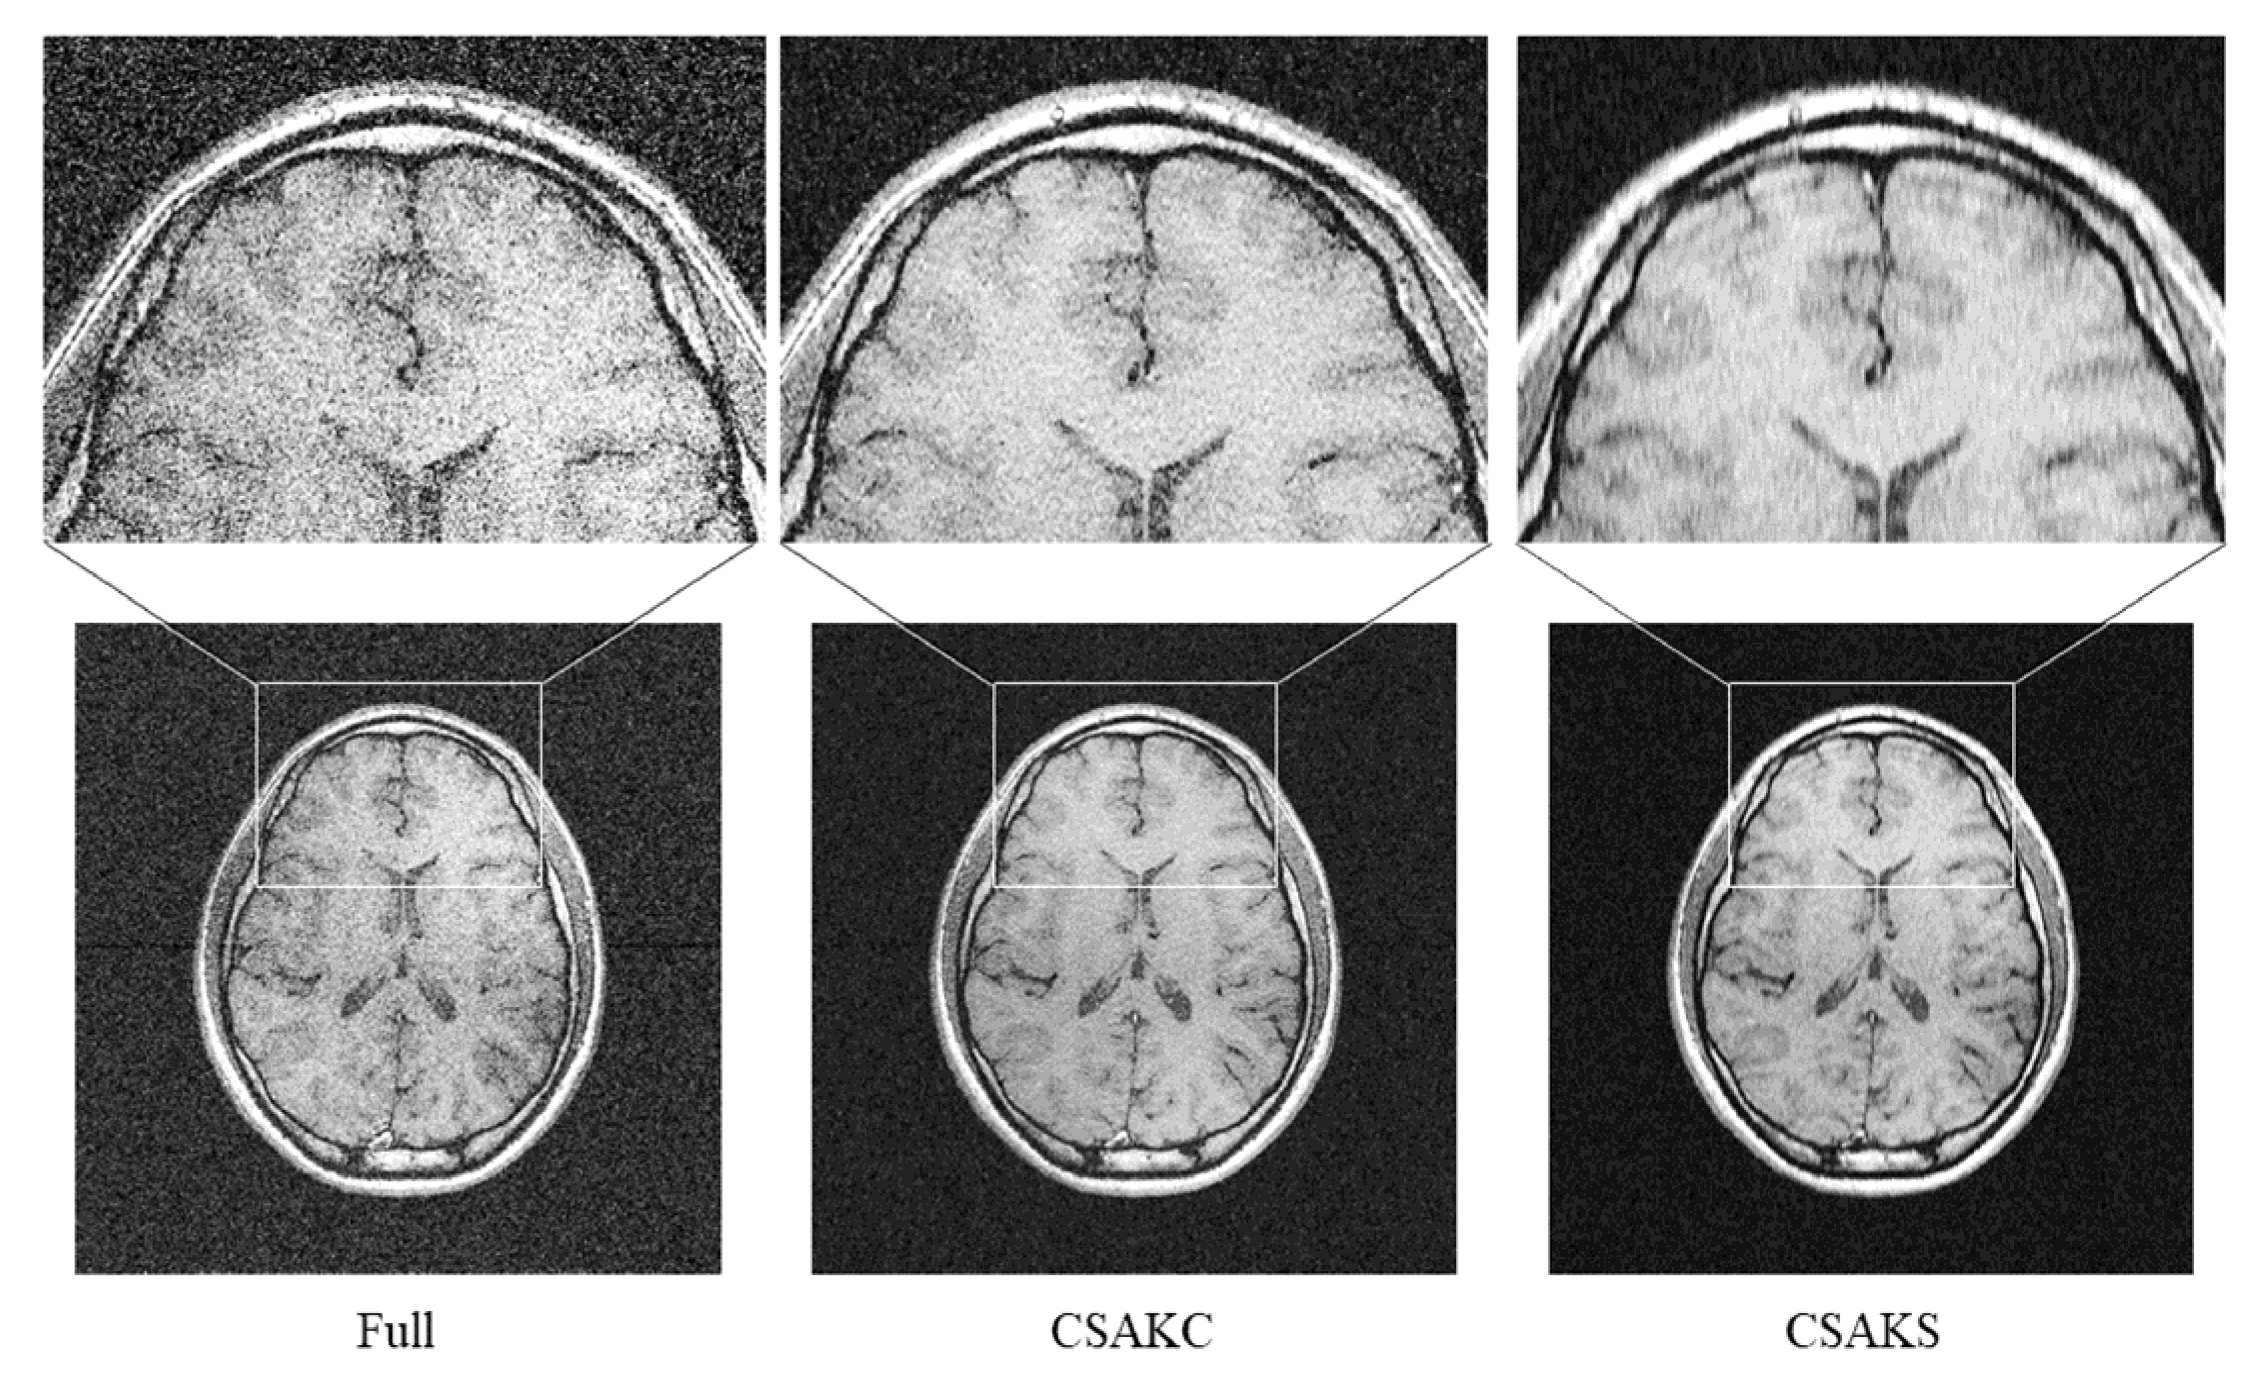

Figure 3.

CSAM, CSAKS, and CSAKC images at different undersampling ratios in the brain phantom. Unlike CSAKC, linear and blurring artifacts can be seen with CSAM and CSAKS. Artifacts are most severe in the CSAM image.

To confirm whether a similar result also occurs in the undersampling ratio acquired from the in vivo human brain, CS reconstruction (TV weight = 0.01, L1 penalty = 0.0001) was performed, and each image was analyzed for comparison. Ringing and blurring artifacts appeared most prominently in the upper part of the CSAKS image with an undersampling ratio of 25%, as in the brain phantom (Figure 5).

Figure 5.

Visual comparison of a full k-space image and CSAK images in a human subject. Although CSAK images were acquired with the same undersampling ratio, the ringing artifacts only occurred when using CSAKS. Note that the acquisition times of the full k-space and CSAK images were 5 m 56 s and 5 m 5 s, respectively.